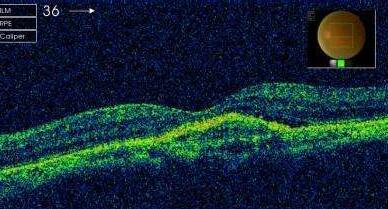

中渗

中渗应该如何医治?